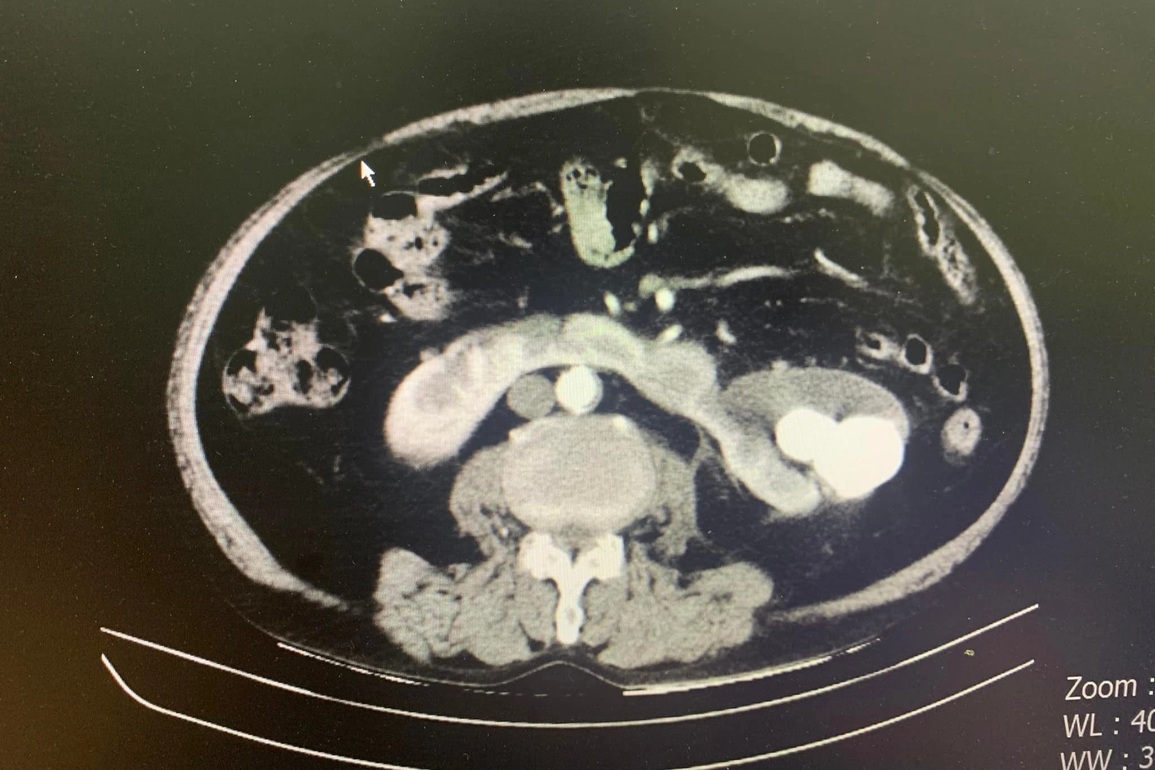

Qua thăm khám, bệnh nhân được chẩn đoán sỏi san hô thận trái, sỏi niệu quản trái trên nền tiểu đường, tăng huyết áp. Đáng chú ý, các bác sĩ phát hiện bệnh nhân mắc một tình trạng hiếm gặp: Thận móng ngựa.

Theo bác sĩ Nguyễn Hồng Long - Khoa Ngoại tổng hợp, Bệnh viện Hữu Nghị, ở người bình thường hai thận sẽ nằm hai bên cạnh cột sống và tách rời nhau. Tuy nhiên ở bệnh nhân bị thận móng ngựa, hai thận sẽ dính vào nhau thành một khối vắt ngang cột sống. Vì thế sẽ dẫn đến các bất thường giải phẫu và khi mổ sẽ dễ gặp tai biến và nguy cơ phải cắt toàn bộ thận là rất cao.

Thận móng ngựa là tình trạng bất thường bẩm sinh. Khi thai nhi vẫn còn trong bụng người mẹ, bệnh sẽ khiến vị trí hai quả thận trong tiểu khung sẽ thấp hơn bình thường. Phần eo giả có thể phát triển đối xứng hoặc không. Phần lớn trẻ sinh ra mắc thận móng ngựa bẩm sinh vẫn có sức khỏe bình thường.